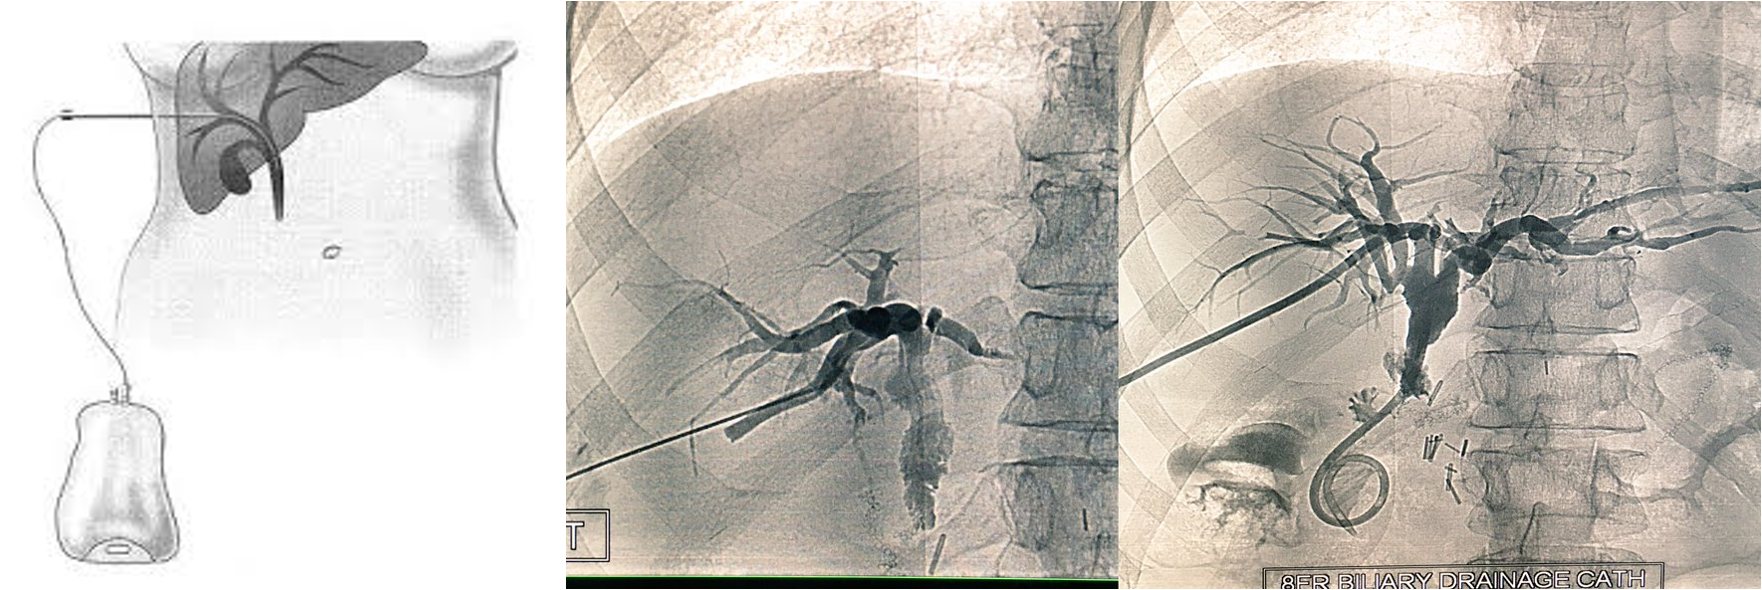

Percutaneous Transhepatic cholangiogram (PTC)